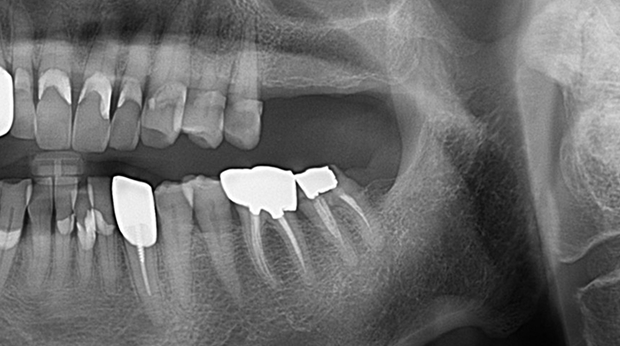

매복 사랑니 발치

임플란트와 사랑니 발치는 외과적 시술로 잇몸을 절개하는 외과적 시술은

짧으면 짧을 수록 시술 후 붓기와 통증이 최소화됩니다.

치과의사 경력 14년차 구강외과 전문의가 빠르고 안전하게, 아프지 않게 수술해 드립니다.